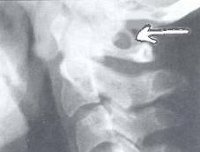

При обращении пациента с симптомами недостаточности кровообращения в вертебро-базилярном бассейне головного мозга в первую очередь производят рентгенографию черепа и рентгенографию позвоночника в шейном отделе. Аномалия Кимерли, как правило, достаточно четко визуализируется на боковых рентгенограммах области краниовертебрального перехода. При наличие ушного шума для исключения лор-патологии (кохлеарный неврит, хронический средний отит, лабиринтит) может потребоваться консультация отоларинголога, проведение аудиометрии и других исследований слуха. Производится также исследование вестибулярного анализатора (вестибулометрии, электронистагмографии, стабилографии).

Наличие косного нароста и возникновение аномалии на верхнем позвонке хорошо отображается на боковой проекции рентгенографии. Причем пациент проходит обычно два этапа – рентген шейного отдела позвоночника и рентген основания черепа.

При жалобах на потерю координации, мышечную слабость, шум в ушах и расстройства зрения пациента направляют на рентгенографию шейных позвонков и головы. Диагностика выполняется в двух проекциях: прямой и боковой.

У большинства больных аномальная костная дуга четко проявляется на боковых снимках атланта в зоне сочленения черепа и шейных позвонков.